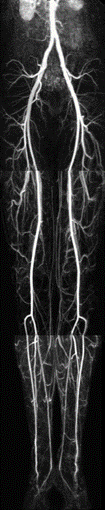

常用血管成像模式的原理和特点(超声多普勒、CTA、MRA、DSA等);